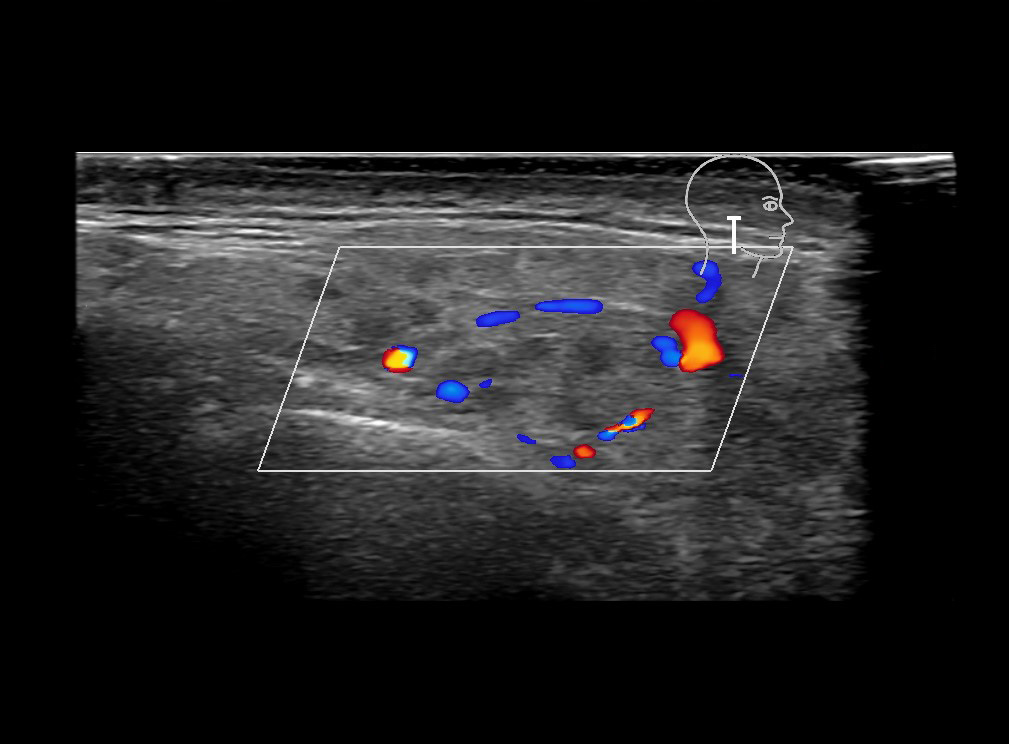

With ultrasound signs of inflammation can be visualized. Edema can be seen as a hyperechoic appearance of the subcutaneous fat, sometimes separated by hypoechoic fluid filled area’s, known as cobblestone appearance. Increased vascularization (hypervascularity) can be seen on colour Doppler. An abscess will appear as a fluid collection appearing as an irregular hypoechoic area with heterogeneous internal echoes and a thickened wall. Posterior acoustic enhancement can be present, and there is vascularity around but not within the mass. Under ultrasound guidance, abscesses can be managed by needle aspirations (18G) under antibiotic cover.

Study the first image to recognize the different layers. If you are sure about the layers, swipe to the second image to view the answer (if applicable).